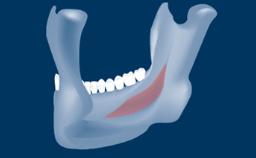

- intraoperative complications of lateral window sinus floor elevation

- intraoperative complications of transcrestal sinus floor elevation